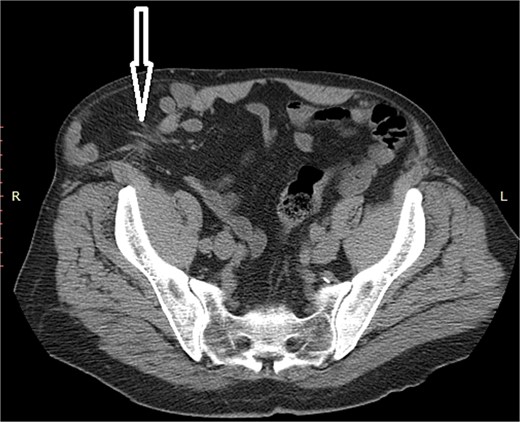

A 72-year-old patient, in good physical condition with a BMI of 26.1, came for an examination due to swelling in the right lateral abdominal wall without swelling of the scrotum. The patient was operated on for a right-sided inguinal hernia as an 8-year-old boy, but there was no appropriate medical documentation for the operative technique used. A month ago, besides the swelling, he experienced occasional abdominal pain and difficulties during physical activities in his garden. During clinical examination, a soft swelling in the right lateral abdominal wall, compressible under palpation was ascertained (Fig. 1). The abdominal ultrasound and contrast abdominal CT showed a thinned right abdominal wall with superficial intestinal loops and the differential diagnosis of a large recurrent inguinal or Spigelian hernia was presumed (Fig. 2). The patient received one dose of prophylactic cephalosporin preoperatively, and was operated on under general endotracheal anesthesia, in a supine position with a lumbar pillow placed for a slight tilt to the left. A right lateral lumbar-inguinal skin incision 4–5 cm above the anterior superior iliac spine in a horizontal direction following the lumbar dermatomal lines was performed. Subcutaneous fat was gently separated and the hernial sac dissection went to its apex below the right costal arch and base to the deep inguinal opening. When the sac was completely freed, the final diagnosis of giant recurrent indirect inguinal hernia (Fig. 3), and the sac with its content was repositioned in the abdominal cavity without opening the abdominal cavity and partial closure of the internal iliac ring was performed with resorptive sutures. After the dissection of the inguinal ligament up to the pubic tubercle (without extending the skin incision) a 15 × 12 cm polypropylene mesh was placed (Fig. 4), fixed to the pubic tuberculum and conjoint tendon with a laparoscopic taker (Fig. 5), and the ileopubic ligament partly with individual and partly with continuous non-absorbable polypropylene 2/0 suture. An opening for the spermatic cord was provided and medially the mesh was fixed with individual resorptive stitches (Fig. 6). The aponeurosis of the external oblique muscle was closed as much as it allowed to be approximated followed by individual subcutaneous and skin stitches (Fig. 7). The operating time was 65 minutes without blood loss and the patient had a quick and satisfactory recovery. He was discharged from the hospital on the third post-op day, and the skin stitches were removed on the 14th day. One month after the surgical treatment the patient was in good condition without any complaints (Fig. 8).

Hernia sac with small intestine loops inside that remained intact during dissection